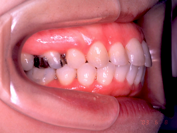

1) 主訴 上の歯が出ており、口が閉じにくい 発音が悪い

2) 診断名 上顎前突

3) 初診時年齢 15歳

5) 抜歯 左右上顎第一小臼歯、下顎左右下顎第二小臼歯(計4本)

6) 治療期間 開始時から装置装着まで3か月、マルチブラケット期間2年3か月、保定期間4年